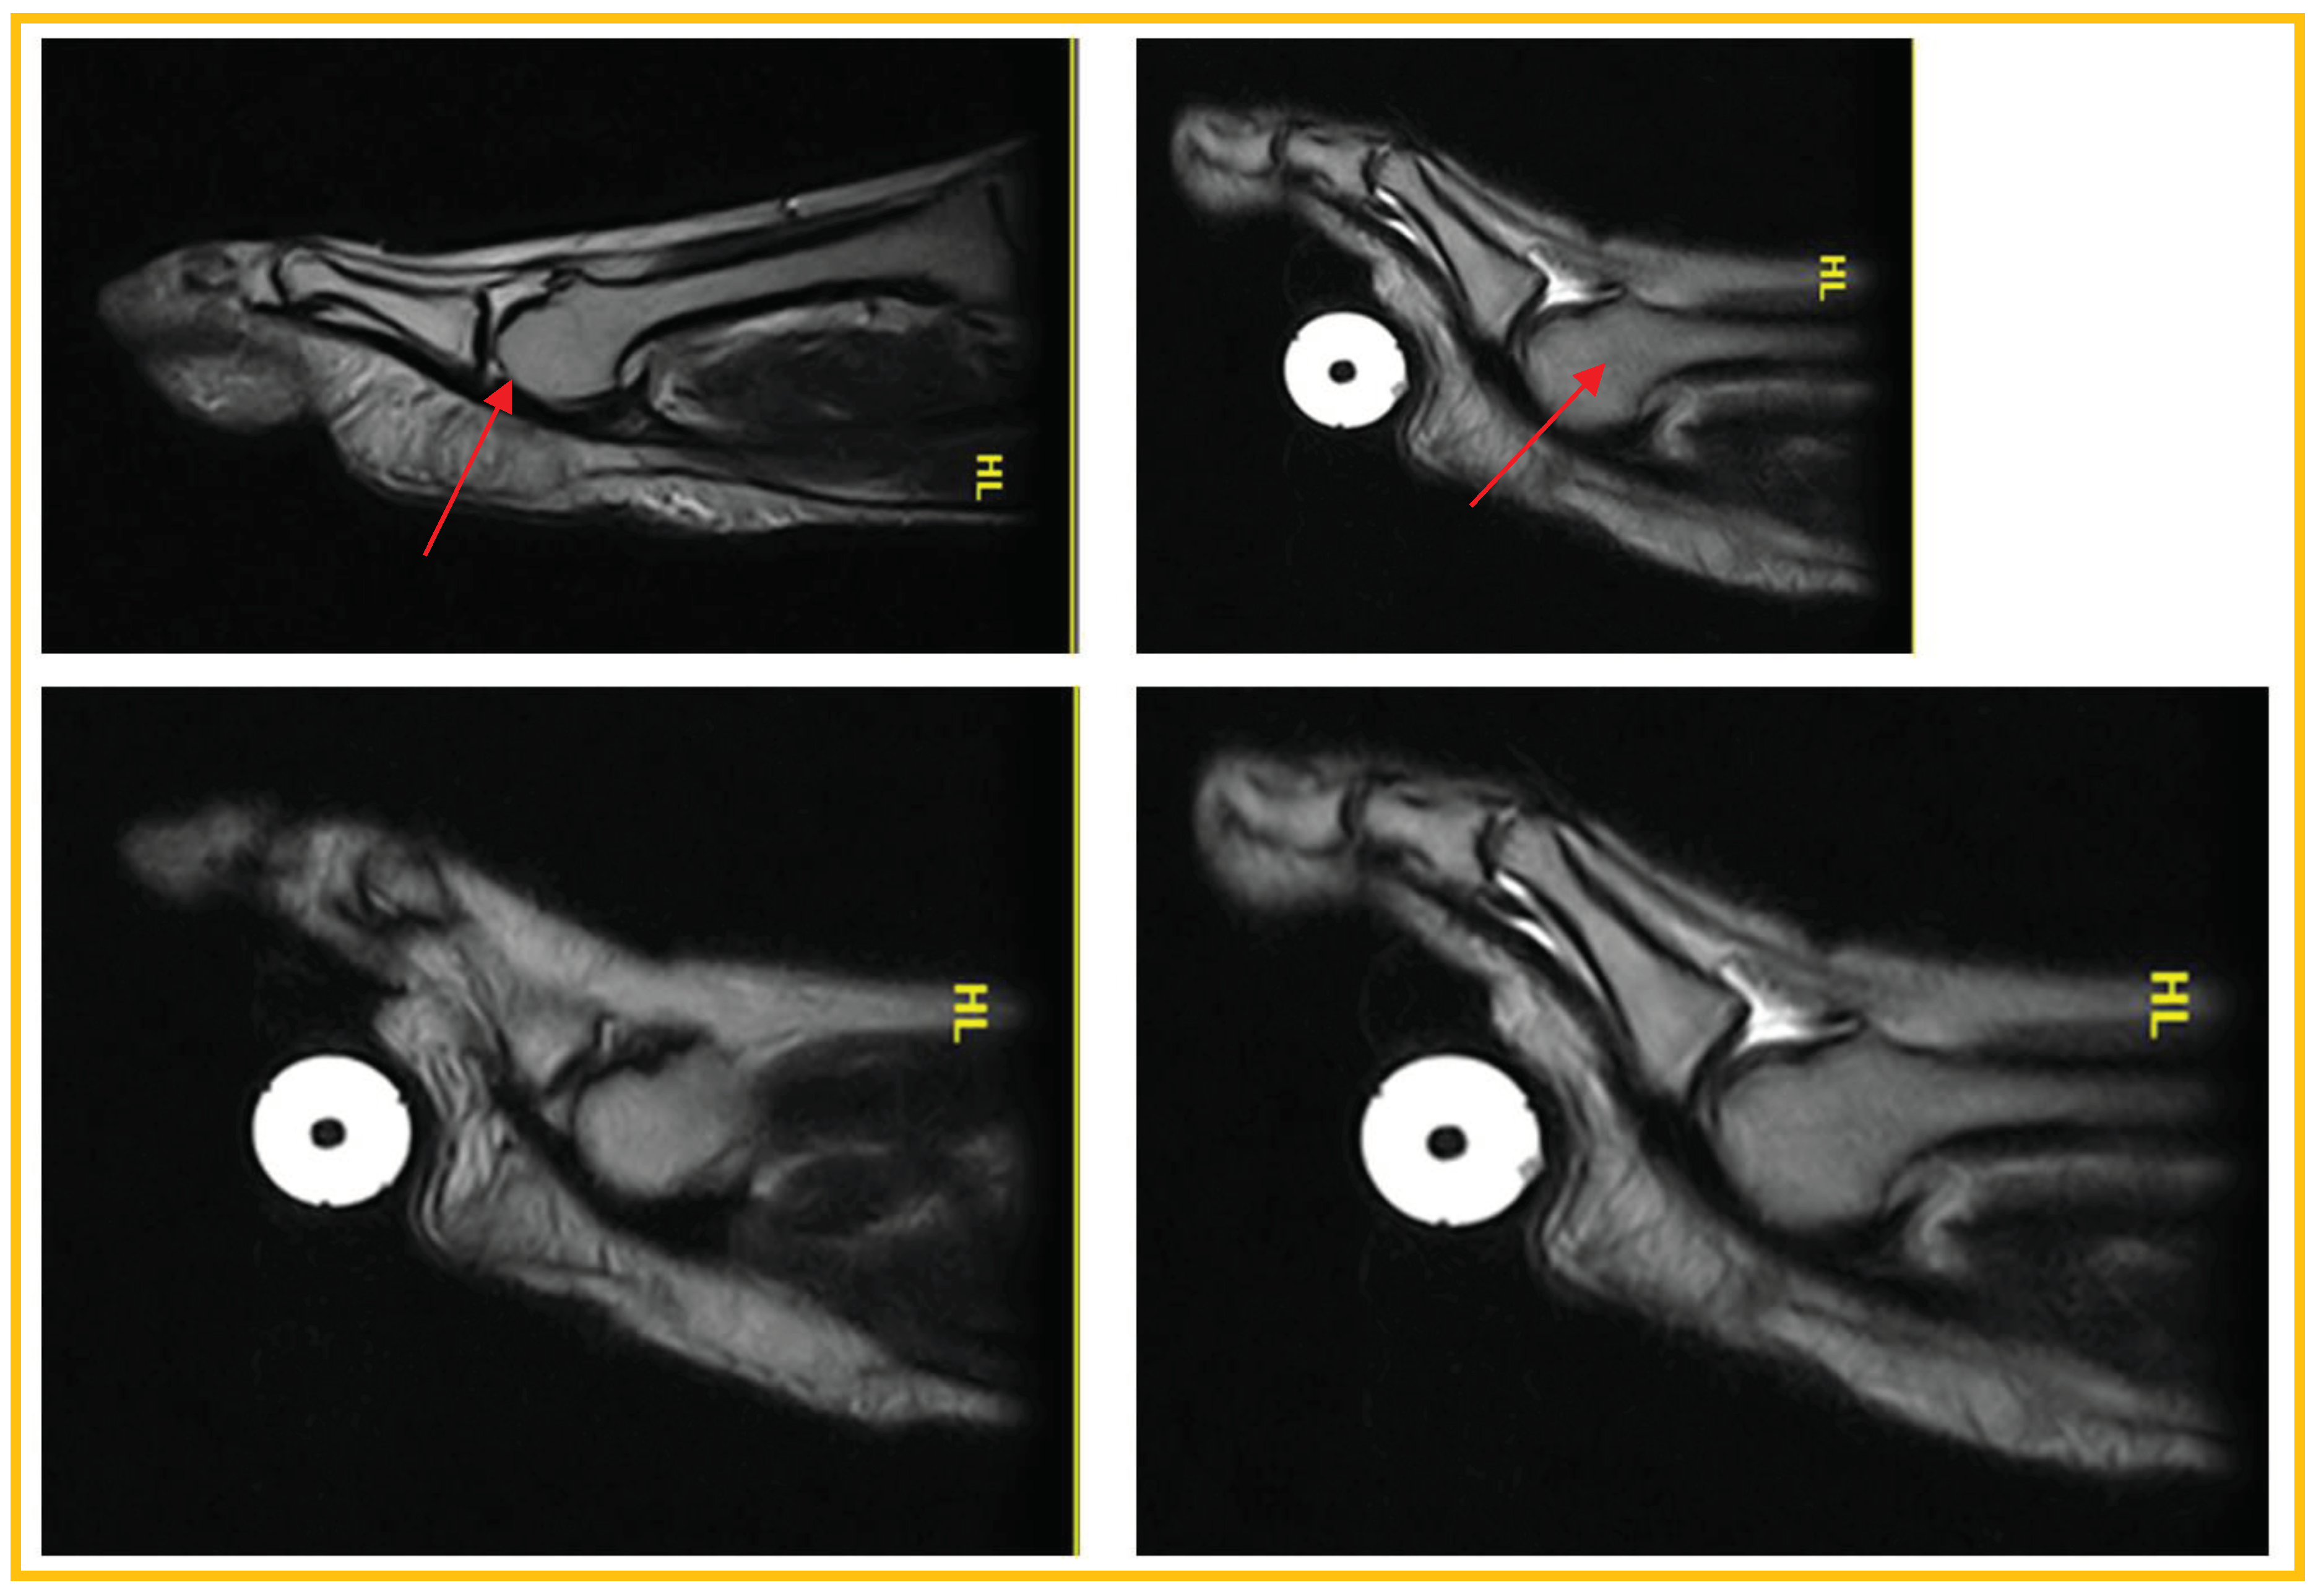

Patient 1:asymptomatic (52 years, male).True negative:Regular PP, homogeneously hypointense both in standard position and during ST (Figure 2)

Patient 2: asymptomatic (34 years woman). False negative (laxity): MF instability (dorsal subluxation of the proximal phalanx) was demonstrated only during TS in the absence of PP tear (Figure 3).

Patient 3: symptomatic (55-year-old woman). True positive: PP lesion visible both in standard position and during ST; dorsal subluxation is highlighted during ST (Figure 3).

In this image, it can be seen that the lesion affects the distal portion of the plantar plate, at the insertion at the base of the proximal phalanx. There is a small interruption of the normal hypointensity of the plate itself superficialy.

Figure 2. True negative.

Figure 3. False negative (laxity).

Figure 4. True positive.